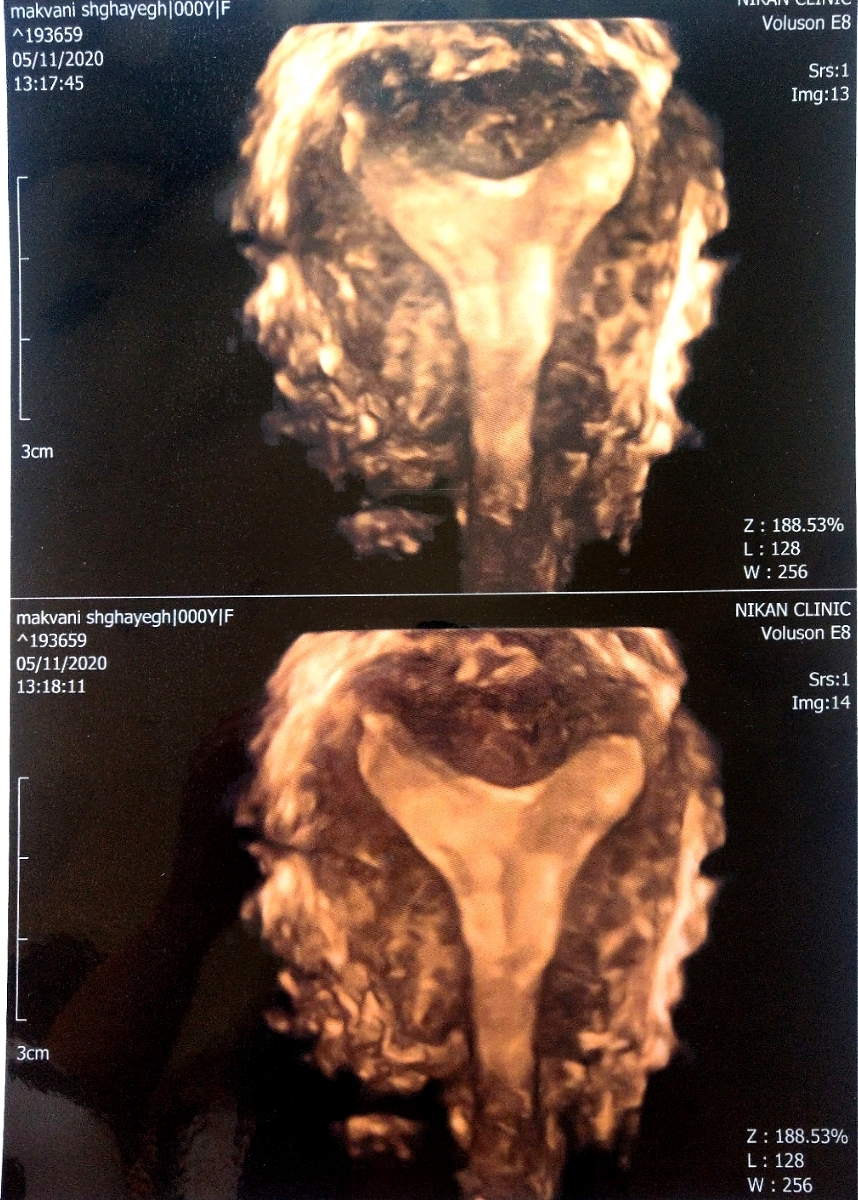

یکی از ویژگی های برجسته 3D USG توانایی آن برای به دست آوردن تصاویر در تجهیزاتی که قبلاً در دسترس نبودند با استفاده از 2D USG است. Coronal plane می تواند اطلاعات دقیقی در مورد رحم و آدنکس ارائه دهد و به ویژه در تشخیص ناهنجاری های مادرزادی رحم مفید است (شکل 1). به همین ترتیب، کف لگن را می توان به طور موثر در سطح محوری با استفاده از USG سه بعدی ارزیابی کرد. علاوه بر این، کاربر توسط این هواپیماهای معمولی محدود نمی شود. ساختن هر صفحه ای از داده های حجم به دست آمده امکان پذیر است.

تصویر سه بعدی از رحم طبیعی. نمای تاجی هم حفره رحم و هم کانتور خارجی رحم را به وضوح نشان می دهد

در سال های اخیر ثابت شده است که 3D USG یک ابزار بسیار قدرتمند برای تشخیص ناهنجاری های رحمی است. مهمترین مزیت USG سه بعدی برای تشخیص ناهنجاری های رحمی، توانایی آن در به دست آوردن نمای تاجی از رحم است که در USG دو بعدی به دلیل وجود لگن استخوانی امکان پذیر نیست. این نما به وضوح خطوط خارجی رحم را مشخص می کند و همچنین اطلاعات دقیقی در مورد شکل حفره ارائه می دهد. در حالت ایده آل، ضخامت آندومتر در طول معاینه باید حداقل 5 میلی متر باشد، زیرا مزایای نمای 3 بعدی تاج در اندومتر نازک تر به میزان قابل توجهی کاهش می یابد

تصویر سه بعدی از رحم کمانی شکل. لطفا توجه داشته باشید که در حالی که کانتور خارجی رحم طبیعی است، فرورفتگی خفیف فوندال در حفره وجود دارد.

تصویر سه بعدی از رحم جدا شده. نمای تاجی به وضوح کانتور خارجی طبیعی رحم و قسمت انتهایی عمیق حفره را به تصویر می کشد.